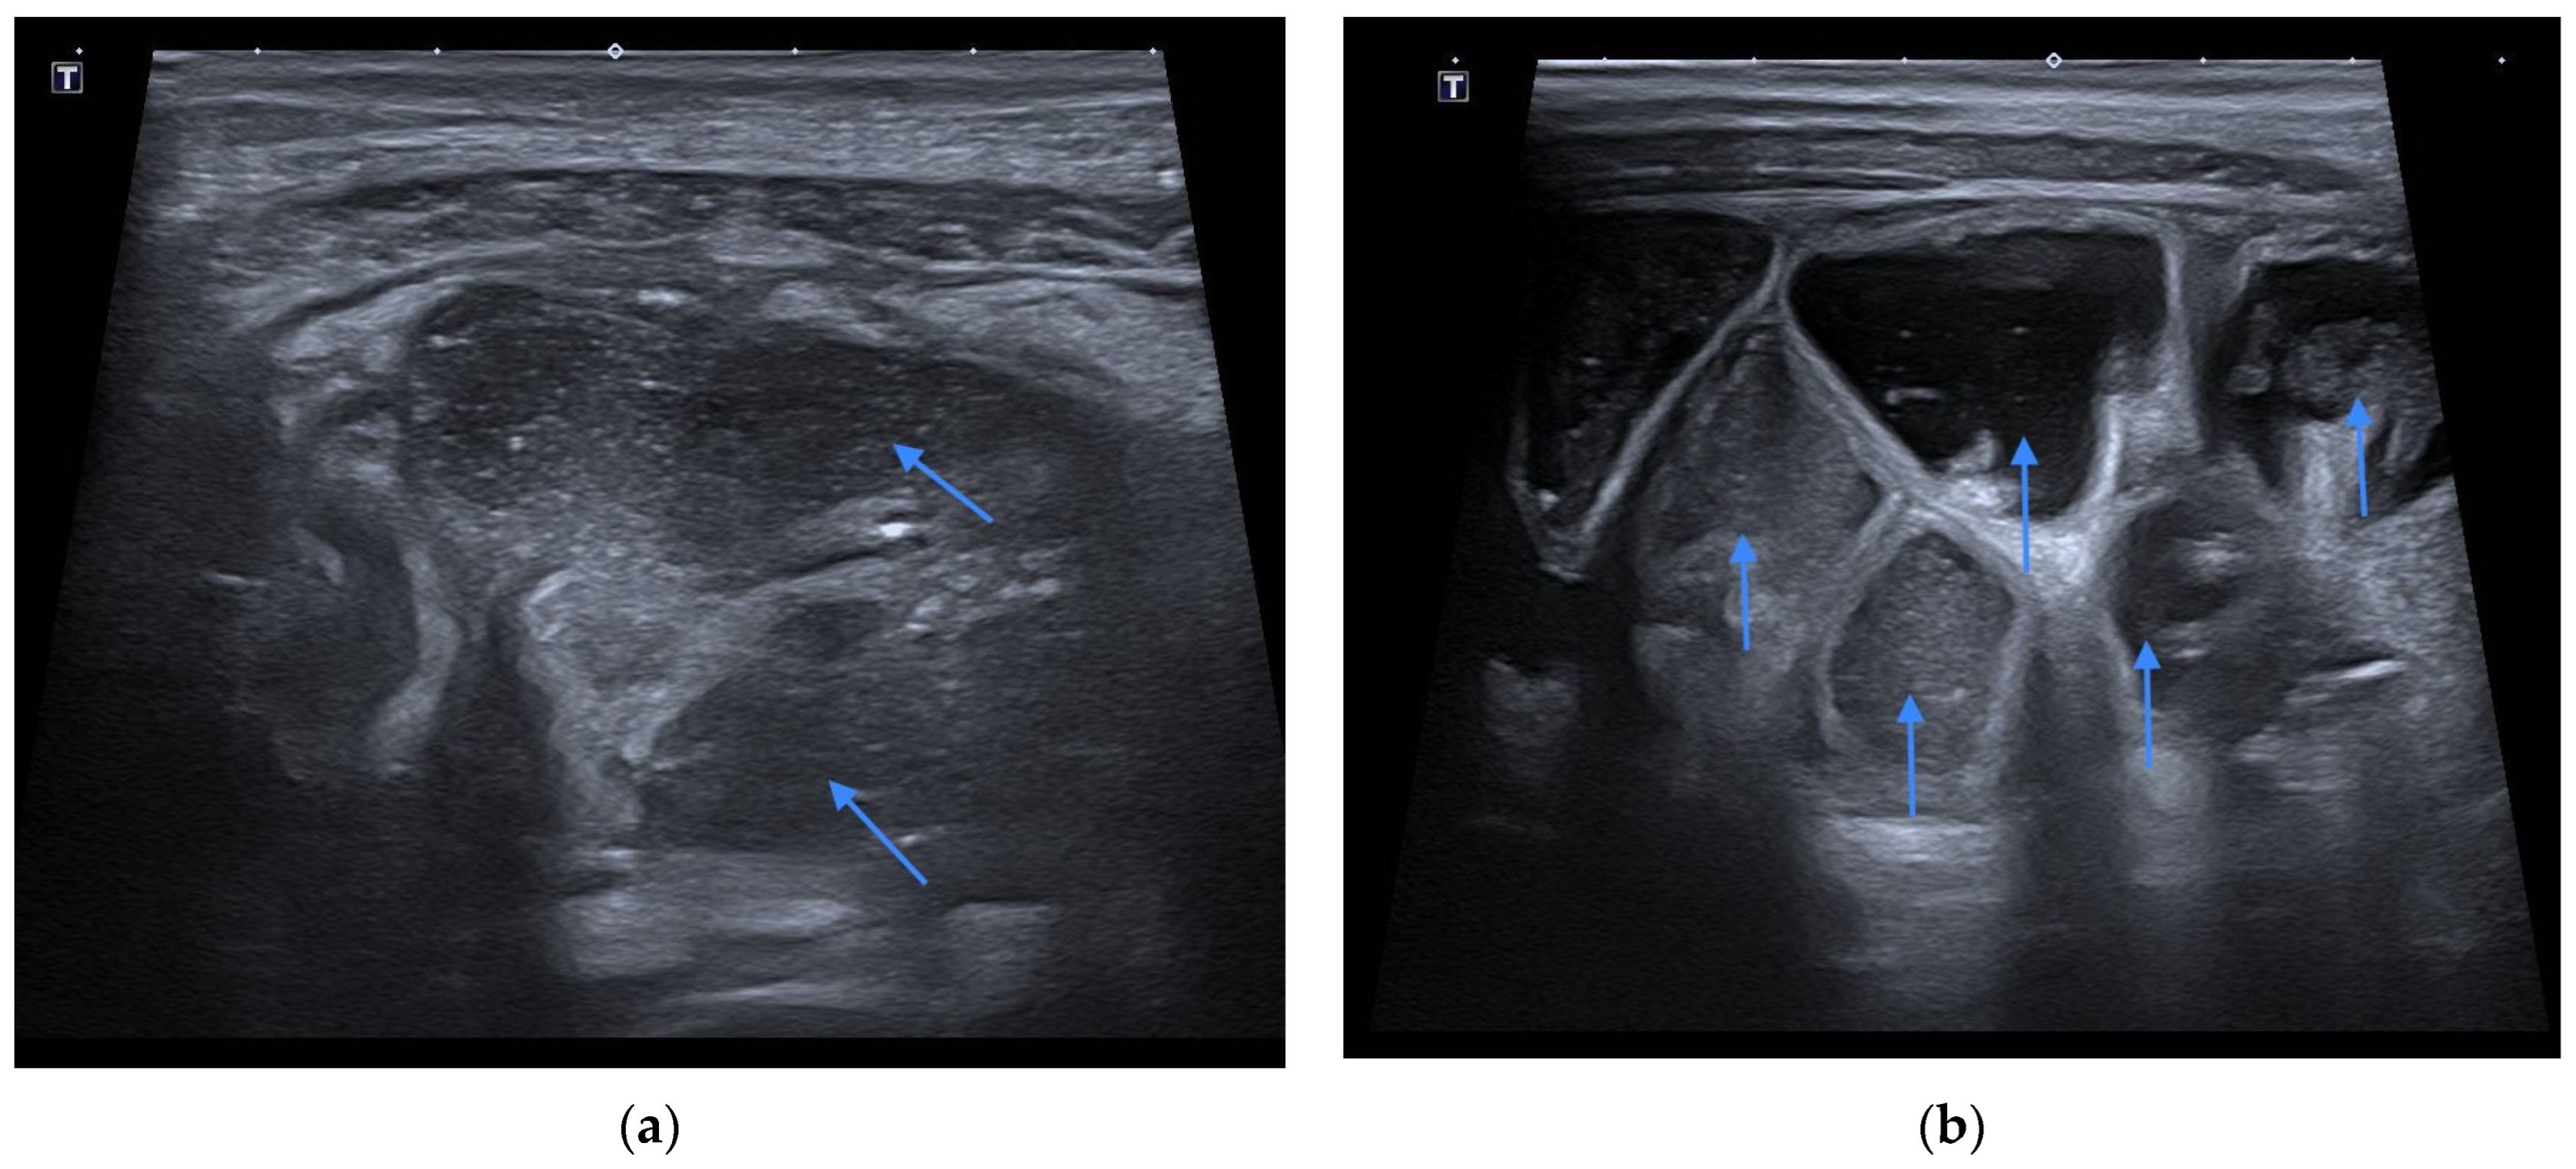

2. Case Presentation